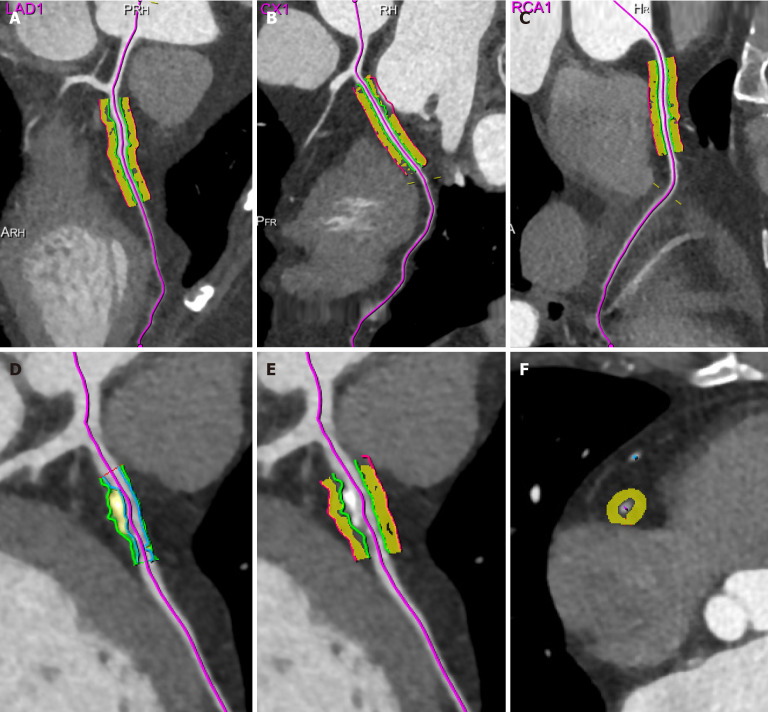

冠状动脉周围脂肪组织(PCAT)与冠状动脉壁双向沟通,在心血管疾病的发病和进展中起着重要作用。近年来,冠状动脉计算机断层扫描测量的PCAT参数已成为量化冠状动脉炎症的潜在无创成像生物标志物,在心血管疾病的早期发现、疾病进展评估、治疗效果评估和预后预测等方面具有重要的临床价值。此外,PCAT放射组学分析等新技术已经拓宽了其在评估冠状动脉斑块易损性、预测心血管事件和改善风险分层方面的潜在应用。本文综述了PCAT研究的最新进展,重点讨论了其在冠状动脉疾病风险识别和炎症监测中的作用,旨在提供基于成像的见解,以支持其在心血管疾病管理中的未来临床应用。

Pericoronary adipose tissue (PCAT) plays an important role in the pathogenesis and progression of cardiovascular diseases due to its bidirectional communication with the coronary artery wall. In recent years, PCAT parameters measured using coronary computed tomography have emerged as potential noninvasive imaging biomarkers for quantifying coronary artery inflammation, with significant clinical value in the early detection, disease progression assessment, treatment efficacy evaluation, and prognosis prediction of cardiovascular diseases. Furthermore, new technologies such as PCAT radiomics analysis have broadened its potential applications in evaluating coronary plaque vulnerability, predicting cardiovascular events, and improving risk stratification. This review discusses recent advances in PCAT research, focusing on its role in coronary artery disease risk identification and inflammation monitoring, and aims to offer imaging-based insights to support its future clinical use in cardiovascular disease management.